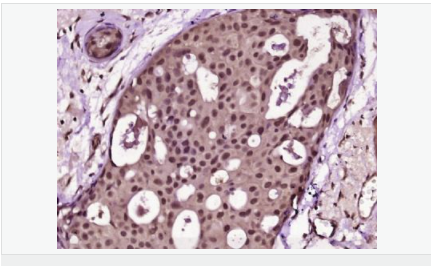

Ki67 antigen is the prototypic cell cycle related nuclear protein, expressed by proliferating cells in all phases of the active cell cycle (G1, S, G2 and M phase). It is absent in resting (G0) cells. Ki67 antibodies are useful in establishing the cell growing fraction in neoplasms (immunohistochemically quantified by determining the number of Ki67 positive cells among the total number of resting cells = Ki67 index). In neoplastic tissues the prognostic value is comparable to the tritiated thymidine labelling index. The correlation between low Ki67 index and histologically low grade tumours is strong. Ki67 is routinely used as a neuronal marker of cell cycling and proliferation.

細(xì)胞增殖標(biāo)志物(Proliferation Marker)

Ki67與PCNA一樣,為細(xì)胞增殖的一種標(biāo)記,在細(xì)胞凋亡中S、G2 、M期均有表達(dá),G0期缺如。

Ki-67增殖指數(shù)高低與許多腫瘤的分化程度、浸潤(rùn)、轉(zhuǎn)移以及預(yù)后密切相關(guān),因此被廣泛作為各種惡性腫瘤的必檢項(xiàng)目之一。